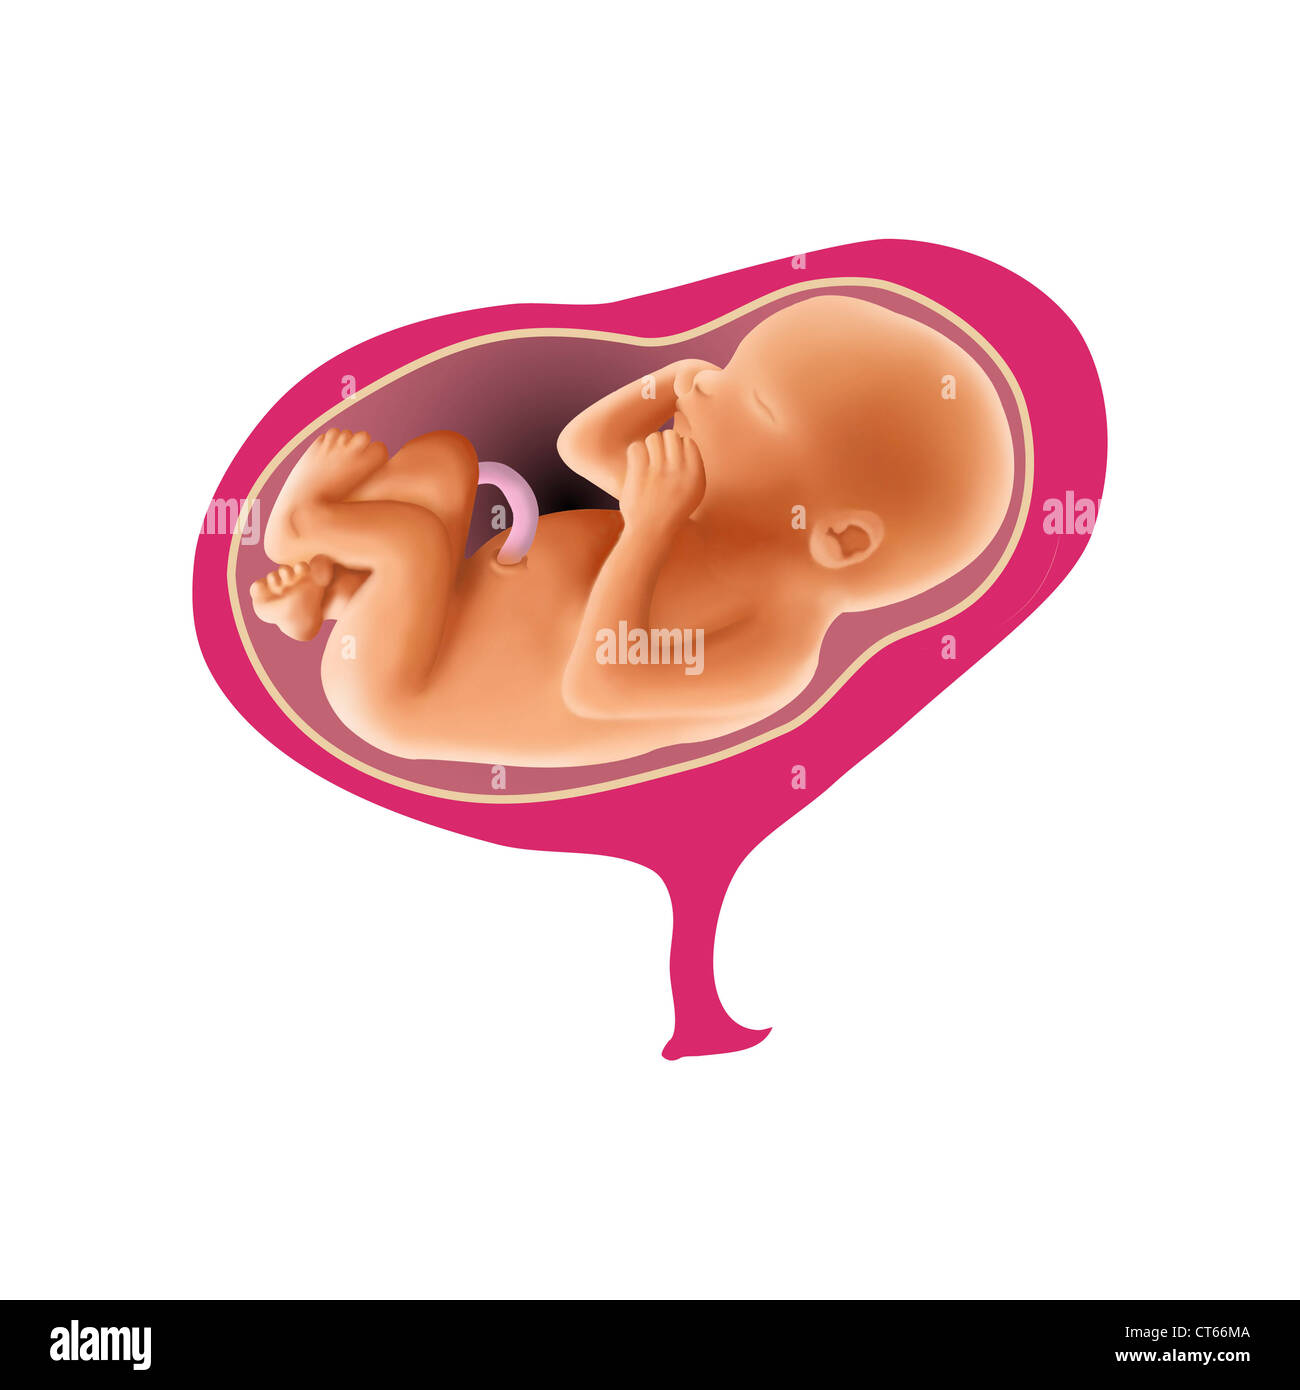

Fetus Stock Photohttps://www.alamy.com/image-license-details/?v=1https://www.alamy.com/fetus-image352771250.html

Fetus Stock Photohttps://www.alamy.com/image-license-details/?v=1https://www.alamy.com/fetus-image352771250.htmlRM2BDX396–Fetus

FETAL SHOULDER PRESENTATION Stock Photohttps://www.alamy.com/image-license-details/?v=1https://www.alamy.com/stock-photo-fetal-shoulder-presentation-49309466.html

FETAL SHOULDER PRESENTATION Stock Photohttps://www.alamy.com/image-license-details/?v=1https://www.alamy.com/stock-photo-fetal-shoulder-presentation-49309466.htmlRMCT66MA–FETAL SHOULDER PRESENTATION

FETAL BREECH PRESENTATION Stock Photohttps://www.alamy.com/image-license-details/?v=1https://www.alamy.com/stock-photo-fetal-breech-presentation-53867030.html

FETAL BREECH PRESENTATION Stock Photohttps://www.alamy.com/image-license-details/?v=1https://www.alamy.com/stock-photo-fetal-breech-presentation-53867030.htmlRFD3HRXE–FETAL BREECH PRESENTATION